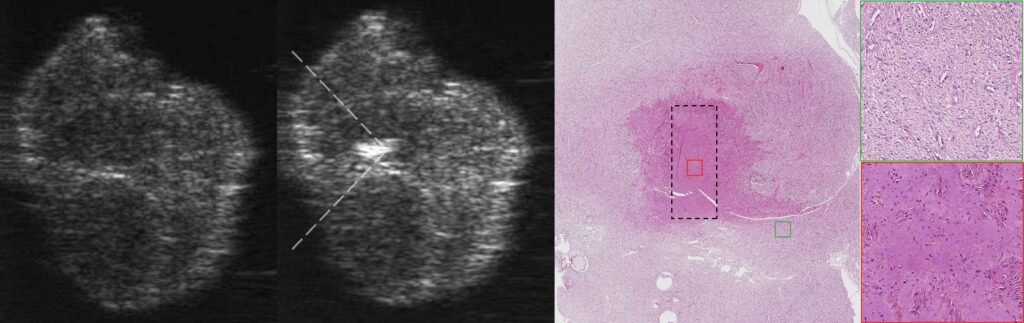

Recently, our team has demonstrated the fundamental possibility of mechanical fractionation of human uterine leiomyoma ex vivo using boiling histotripsy leading to target tissue liquefaction down to subcellular fragments as was confirmed histologically.

Currently, LIMU is leading the research on a larger sample batch to study the response of various uterine tumors to mechanical fractionation with boiling histotripsy, the influence of their elastic properties on this response, as well as to determine the optimal range of exposure parameters for the effective and rapid fractionation of such neoplasms.